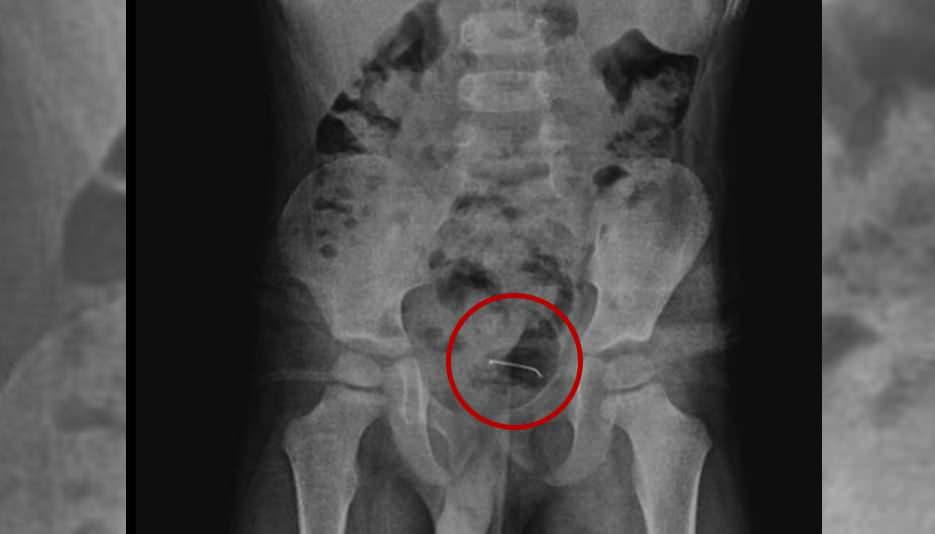

5 yaşındaki çocuğa yapılan tetkikler sonucunda, şiddetli karın ağrısına neden olan durumun mesane duvarına yapışan yabancı unsur olduğu tespit edildi. Küçük çocuğun yuttuğu 3 santimetre uzunluğundaki toplu iğne başarılı bir operasyonla alındı.

Kamçı, yabancı cismin bedenden olağan yollarla atılamadığını belirterek, “Bunun üzerine ameliyat kararı aldık. Ameliyatta cismin mesane duvarına yapıştığını gördük. Cerrahi operasyonla 3 santimetre civarındaki toplu iğneyi çıkardık. Hastayı birkaç gün takipte tuttuk. Genel sıhhat durumu âlâ olan hastamızı taburcu ettik.” ifadelerini kullandı.